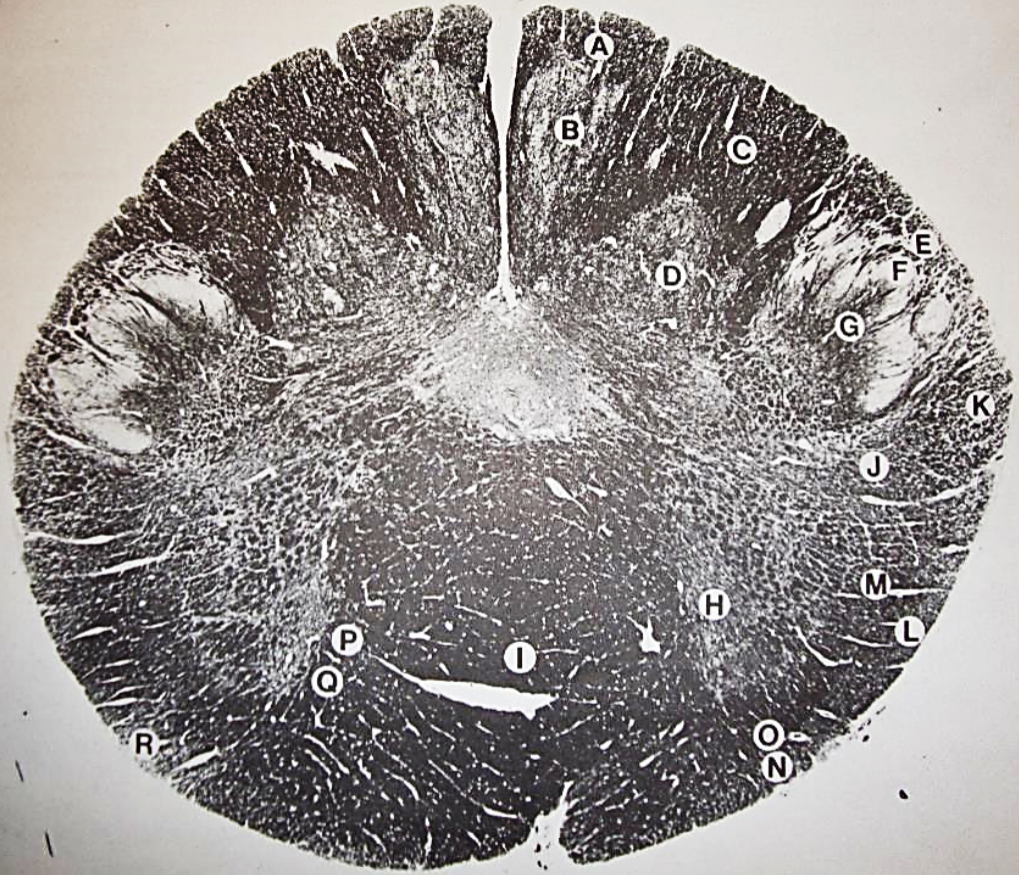

A

posterior median sulcus

B

posterior intermediate sulcus

C

anterior median fissure

D

gracile fasciculus

E

Gracile nucleus

F

fasciculus cuneatus

G

spinal trigeminal tract

H+I collectively

spinal trigeminal nucleus

J

Accessory nucleus

K

pyramidal decussation

L

lateral corticospinal tract

M

rubrospinal tract

N

posterior spinocerebellar tract

O

anterior spinocerebellar tract

P

lateral spinothalamic tract

Q

anterior spinothalamic tract

R

lateral vestibulospinal tract

S

medial longitudinal fasciculus

T

tectospinal tract

U

central canal